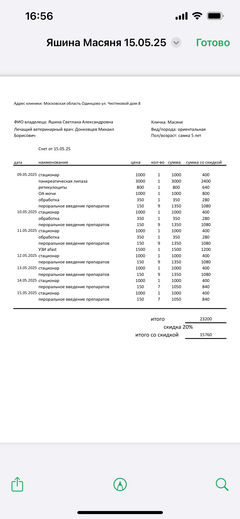

Была куплена в питомнике взрослой. У Масяни начались проблемы с кишечником и она стала подтекать и все пачкать. Надо отдать должное хозяевам - ее обследовали вдоль и поперек - как говорили местные врачи, сдавали много анализов но диагноза так и не поставили.

Ярко выраженная болезненность в области крестца, на обезболе полегче. По результатам приема невролога проведена миелография - множественная компрессия, возможно опухоль, возможно грыжа, нужно удалять...